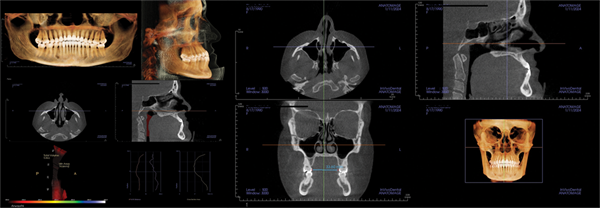

Patient two: Palatal expansion and Phase I (Figs. 4–7)

The second patient was a 7½-year-old boy referred for crowding. During the examination, it was noted that he snored, was a mouth breather, and had nocturia.

The facial examination showed well-balanced jaw relationships and narrow smile bones, resulting in a lack of a full smile. The panoramic X-ray showed anterior crowding, adequate room for the second molars, and a Class II tendency. The lateral X-ray confirmed the Class II tendency.

The airway view on CBCT demonstrated an MCA of 60 and enlarged adenoids. The palatal width was 28 mm. The parents were advised to consult an ENT surgeon, and Phase I treatment was initiated to include palatal expansion.

Following expansion, and before completing Phase I treatment with aligners, the MCA increased to more than 200 mm. The palatal width increased to 34 mm. The ENT surgeon did not recommend surgical intervention at that time. The parents reported improved sleep and resolution of enuresis.